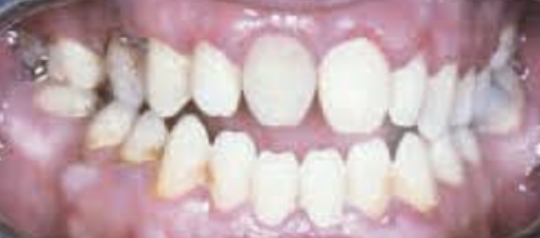

Wat is de klasse III afwijking?

Dit heet ook wel een mesiorelatie. De eerste ondermolaar staat een premolaarbreedte meer naar mesiaal ten opzichte van de eerste bovenmolaar dan bij een neutrorelatie. De onderkaak staat hierbij een stuk naar voren, en de onder incisieven staan voor de boven incisieven. Deze afwijking kan ook variëren naar meer of minder premolaarbreedte.